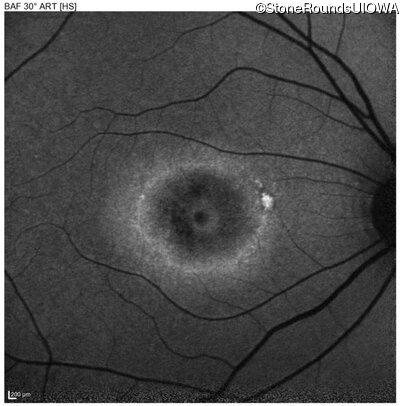

AD Stargardt Disease (IIF)

Age at visit: 40 years

This 40 year old woman first noticed a reduction of her visual acuity about two years ago. She has been sensitive to light for as long as she can remember.

AD Stargardt Disease PROM1 Arg373Cys CGC>TGC   AD